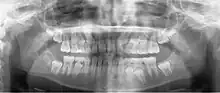

A panoramic radiograph of a 9 year old in mixed dentition

A basic panoramic radiograph